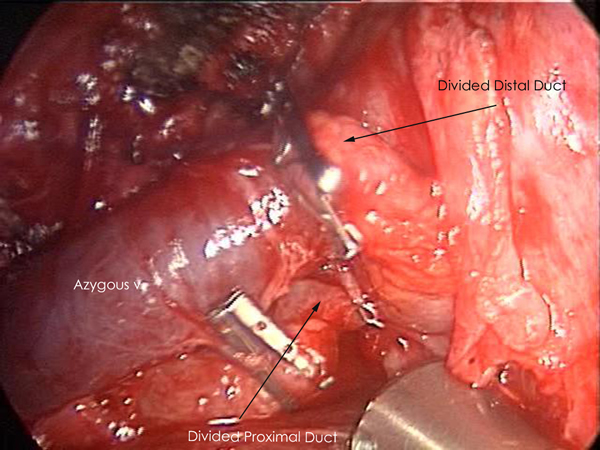

General anesthesia with single lung ventilation is required and the duct is always approached through the right chest due to its constant position in the lower right chest (Figure 1). The patient is placed in a left lateral decubitus position, rolled forward, and flexed to allow increased exposure of the posterior mediastinum. An epidural is not necessary and intercostal blocks with 0.25% bupivacaine can be used for analgesia. The thoracoscope is placed in the seventh intercostal space along the line of the anterior superior iliac spine and the working incision (5cm) is placed in the fifth or sixth intercostal space in the anterior axillary line (Figure 2). The soft tissues of the chest wall are kept open with a Weitlaner retractor and the intercostal incision is made longer than the skin incision. This allows for the introduction of two or three instruments through this incision and allows suction to be applied within the chest without causing re-expansion of the lung. A third incision is made at the level of the dome of the diaphragm after visualizing the desired space thoracoscopically. This incision is placed along the mid-axillary line.

| Figure 1: CT Chest showing thoracic duct. | Figure 2: Thoracoscopic port placement. | Figure 3: Inferior Pulmonary Ligament Division. |